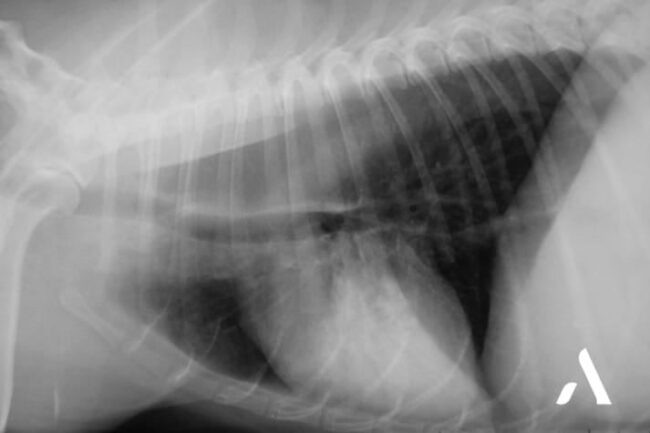

Chaque mercredi l’équipe d’imagerie d’Advetia vous propose de tester vos connaissances avec un cas clinique tout en image. Commémoratifs Chien Rottweiler mâle âgé de 4 ans, présenté pour abattement, hyporexie et dyspnée observés depuis 8 jours. Technique Radiographies sans préparation du thorax en incidence de face (DV) et de profil droit. Interprétation Il existe une…